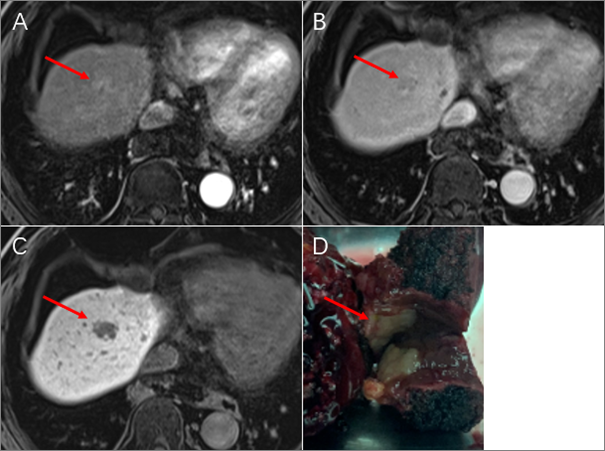

肝脏影像报告和数据系统肝癌mri辅助征象解析